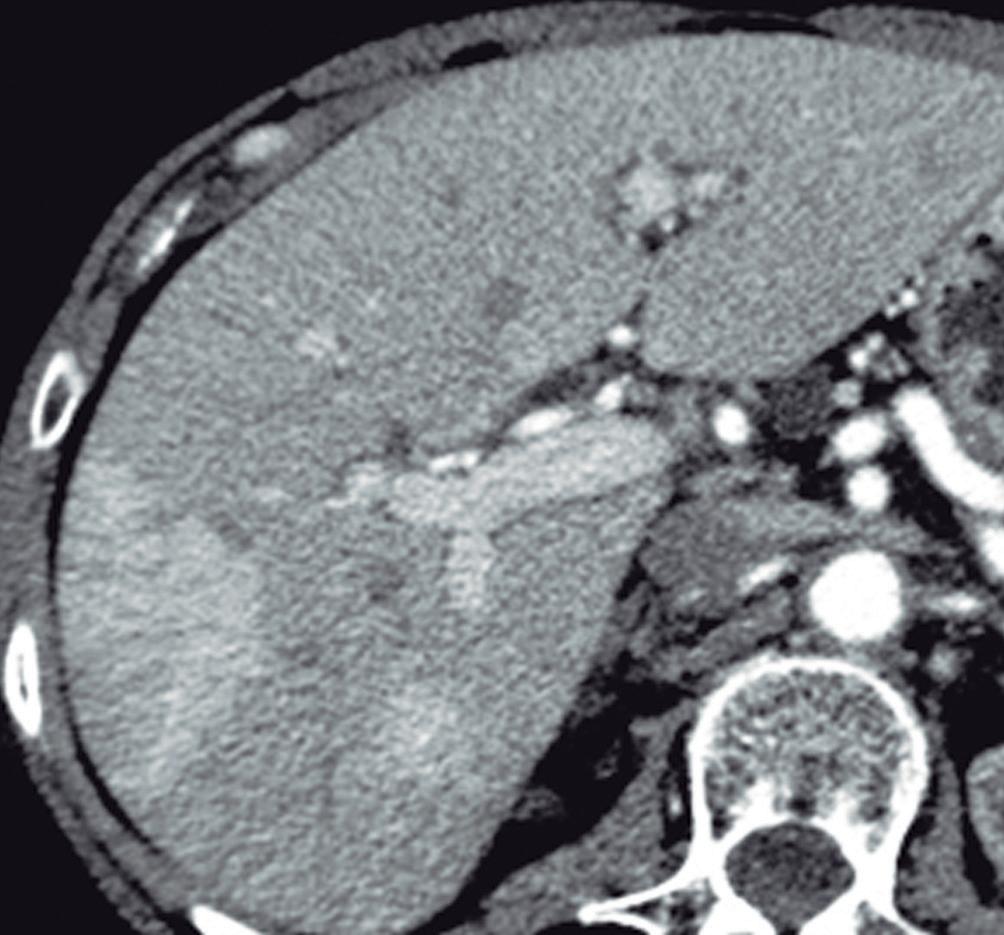

La HNF se manifiesta como uno o más nódulos (múltiple en aproximadamente 20%) de bordes netos y contornos lobulados. En la TCMC tiene densidad similar o apenas menor a la del parénquima adyacente. Si la cicatriz es visible (60%) en la TC es hipodensa. (Figura 3) En la RM su señal es isointensa o apenas hipo o hiperintensa en T1 e isointensa o un tanto hiperintensa en T2. (Figura 4) La cicatriz es hiperintensa en T2 (visible 80% en la RM), característica clave para diferen-

Figura 3. HNF en la tomografía computada A: Imagen en plano coronal de tomografía computada en fase arterial con reconstrucción MIP (máxima intensidad de proyección), demuestra una lesión sólida exofítica en el sector caudal del segmento IVb. Tiene bordes netos y contornos algo lobulados y exhibe hiper refuerzo en fase arterial. En el centro se aprecia una zona de menor densidad que sugiere una cicatriz. También nótese una pequeña imagen de similar aspecto ubicada en el segmento V. B: Imagen en plano coronal en la fase venosa portal que ilustra como la lesión se ha hecho isodensa con el parénquima y es imperceptible. Sólo se sospecha por la deformación del contorno que produce su crecimiento exofítico.

B

A: En el domo hepático se observa en la secuencia T2 con supresión grasa un nódulo sólido que tiene una señal levemente hiperintensa con respecto al parénquima. Tiene bordes netos. Presenta una cicatriz central de mayor intensidad de señal. B: Imagen en secuencia T1 obtenida en fase arterial que demuestra el hiperrefuerzo de la lesión con excepción de su cicatriz central. C: Imagen en fase portal en la que se puede apreciar que la lesión sólo conserva una leve hiperintensidad con respecto al parénquima. Persiste sin refuerzo la cicatriz central. D: Imagen obtenida en fase de equilibrio. La lesión sólo muestra una hiperintensidad sutil y se puede apreciar el refuerzo tardío de la cicatriz, típico de la HNFl.